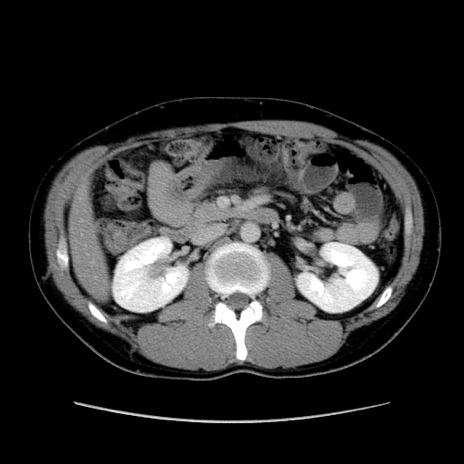

症例36(横断像)

冠状断像

【症例】20歳代 男性

【主訴】心窩部痛

【現病歴】今朝より上腹部痛あり。一旦軽快していたが再度出現したため救急要請。昨日夕に白身の魚を含む刺身を食べた。

【身体所見】BP 136/89mmHg、HR 74/min、BT 37.0℃、腹部:膨満、軟、心窩部に圧痛あり。反跳痛なし、筋性防御なし、腸雑音やや亢進あり。

【データ】WBC 17700、CRP 0.48